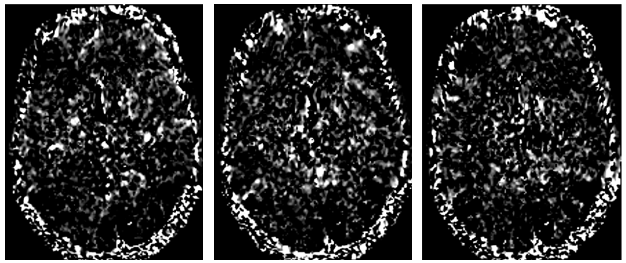

Refer to caption

Figure 1: Examples of a transverse section beta coefficient images for subject #1 in the NSD dataset. These volumes were acquired while watching samples 1, 6, and 8 (from left to right) of the test set. For each volume, the transverse section at voxel 80 was considered and values below the 40th40^{th} percentile and above the 95th95^{th} percentiles were saturated to pure black and white respectively.

The fMRI-stimulus pairs were obtained by the open-source Natural Scenes Dataset (NSD)  [1]. This comprised 7T fMRI recordings, along with BOLD signals, from eight healthy participants. During continuous acquisitions, they viewed natural color images, taken from the Common Objects in Context (COCO) dataset [15]. COCO images were 425×425 pixels and accompanied by a description in English natural language. The beta coefficients were computed using data in the NSD (Fig. 1), according to the methodology described in sec. 3.1) . In NSD, pre-defined ROIs were available for each subject, allowing to focus on relevant voxels and distinguish between low-level visual areas (such as V1, V2, V3, and V4) and higher-order visual areas involved in recognizing faces, places, words, and body parts within the inferior temporal cortex. Z-score normalization was applied to beta values, multiplying each sample by the mean and dividing by its standard deviation, both computed on the entire dataset. According to the literature [30, 21], 90% of the samples was used to build the training set, while the remaining 10% composed the test set. Out of the eight participants, just four (#1, #2, #5, and #7) were retained for this study because they underwent the full acquisition protocol. As an example, for subject #1, 37 acquisition sessions were performed, each acquisition involving 750 stimulus images (administration time 4 s). For each stimulus, the BOLD signal was acquired in that time frame. General model transform mapped the BOLD signal into the beta values. After applying the above-cited ROIs, 9,841 one-dimensional vectors of beta values were attained, each composed of 15,724 elements.